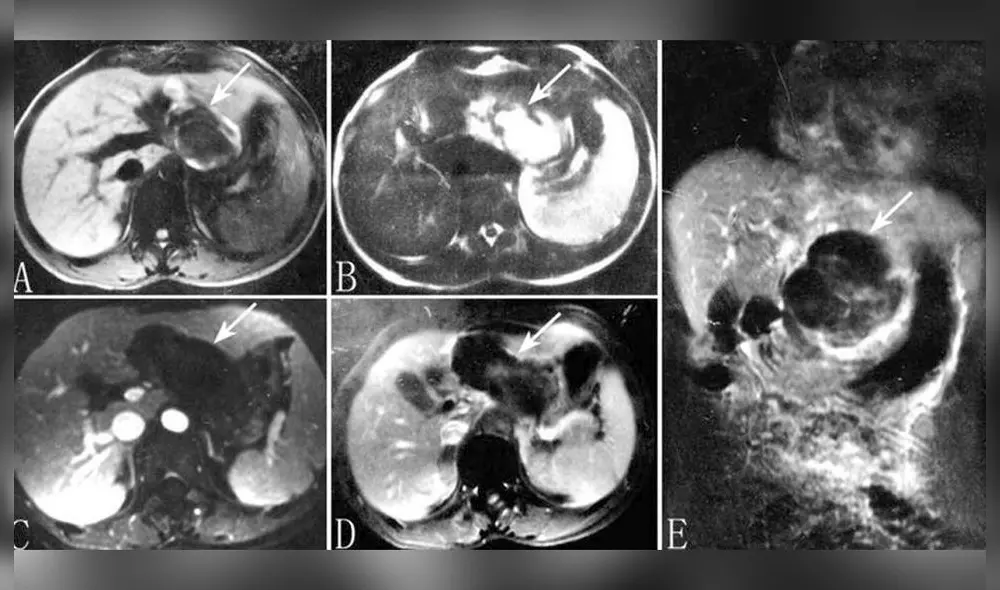

La paciente había presentando sangrado menstrual durante dos semanas seguidas después de 49 días desde su última regla. Se procedió a hacerle un ecografía posterior que reveló que había un bebé en su hígado.

En el caso de su paciente, el embrión viajó hasta el hígado y se implantó allí.